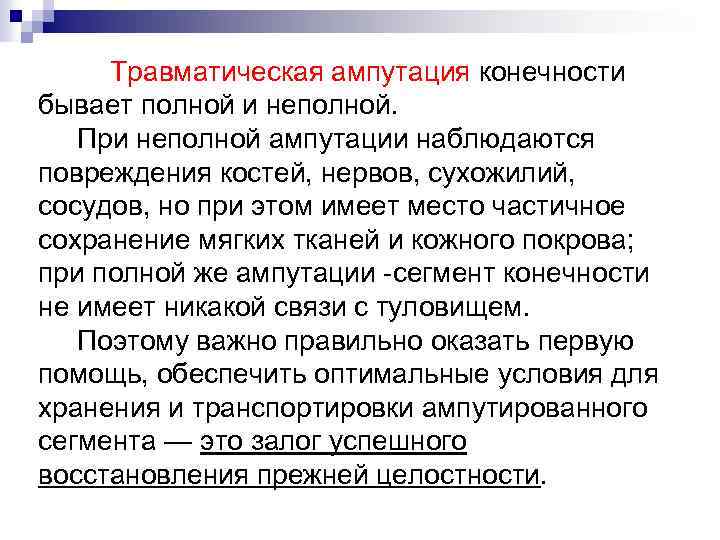

Травматическая ампутация конечности бывает полной и неполной. При неполной ампутации наблюдаются повреждения костей, нервов, сухожилий, сосудов, но при этом имеет место частичное сохранение мягких тканей и кожного покрова; при полной же ампутации -сегмент конечности не имеет никакой связи с туловищем. Поэтому важно правильно оказать первую помощь, обеспечить оптимальные условия для хранения и транспортировки ампутированного сегмента — это залог успешного восстановления прежней целостности.

Травматическая ампутация конечности бывает полной и неполной. При неполной ампутации наблюдаются повреждения костей, нервов, сухожилий, сосудов, но при этом имеет место частичное сохранение мягких тканей и кожного покрова; при полной же ампутации -сегмент конечности не имеет никакой связи с туловищем. Поэтому важно правильно оказать первую помощь, обеспечить оптимальные условия для хранения и транспортировки ампутированного сегмента — это залог успешного восстановления прежней целостности.